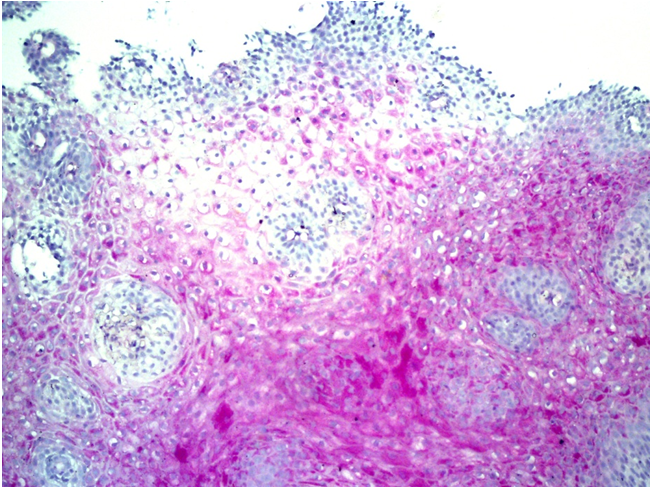

An immunohistochemical study predominantly showed mild to moderate positive membrane claudine 1 expression in some cases (score 1 or 2), from 25 to 50% (score 1 and 2) of epithelial cells. The total expression score ranged from 3 to 6, H-score expression was mainly 1-2 (Figure 3), which reflected the damage to the tight junctions of the esophageal epithelium.

Figure 3 Fragment of the esophagus, mildly expressed (score up to 1), focal (up to 20%-30% of the epithelial cell membranes) expression of the protein of tight junctions of claudine 1. IHC with claudine 1, 50x magnification.